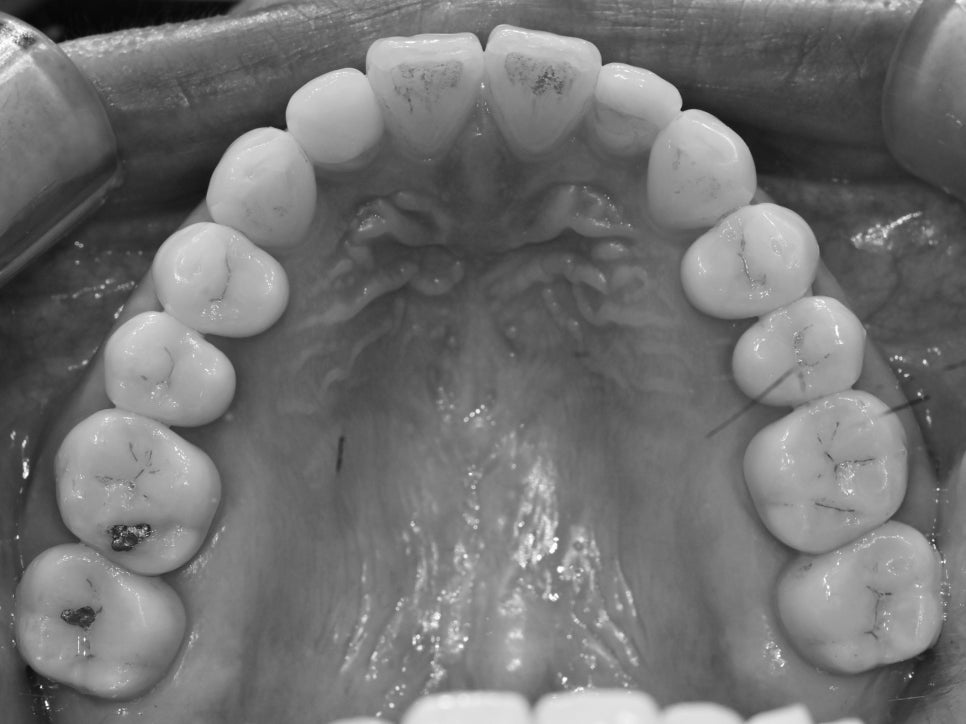

먼저 상악과 하악 교합면을 보겠습니다.

위쪽은 대체적으로 고르게 배열되어 있습니다.

그러나 아래 앞니를 보셨을 때,

다소 불규칙한 배열임을 알 수 있습니다.

다행스러웠던 부분은 심하게 틀어지지 않았기에

충분히 부분교정 방식으로 해결해볼 수 있습니다.